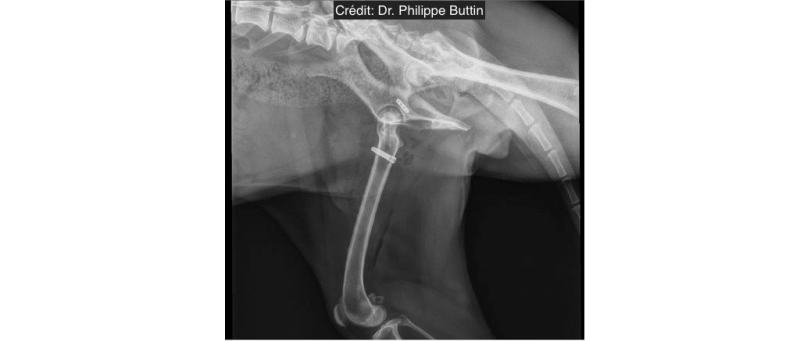

Extra-articular stabilization of craniodorsal hip dislocation

Extra-articular stabilization of caudo-ventral hip dislocation

Hip dislocation : Round ligament reconstruction

Radiologické snímky